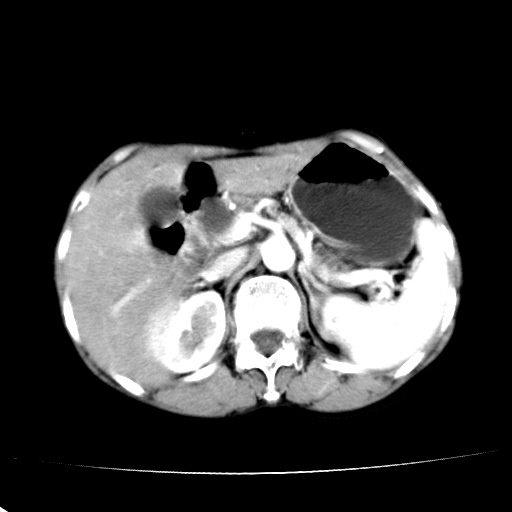

以下是引用jiangjing在2008-6-3 13:36:00的发言:[br]支持 胰头癌------肝内外胆管扩张,胰管扩张,胰头增大,增强见结节状轻度强化影,双管征明显

以下是引用卜一在2008-6-3 14:40:00的发言:[br]支持:胰头癌!(肝内外胆管扩张,胆囊高度扩张,胰管扩张,胰头增大,增强见结节状强化,明显低于胰腺强化密度,并明显见双管征)

以下是引用dyqct在2008-6-3 14:54:00的发言:[br]支持 胰头癌伴肝内外胆管扩张,胰管扩张,胰头增大,增强见结节状轻度强化影,双管征明显。肠系膜上静脉已受侵(已不能手术),建议离子植入治疗吧。